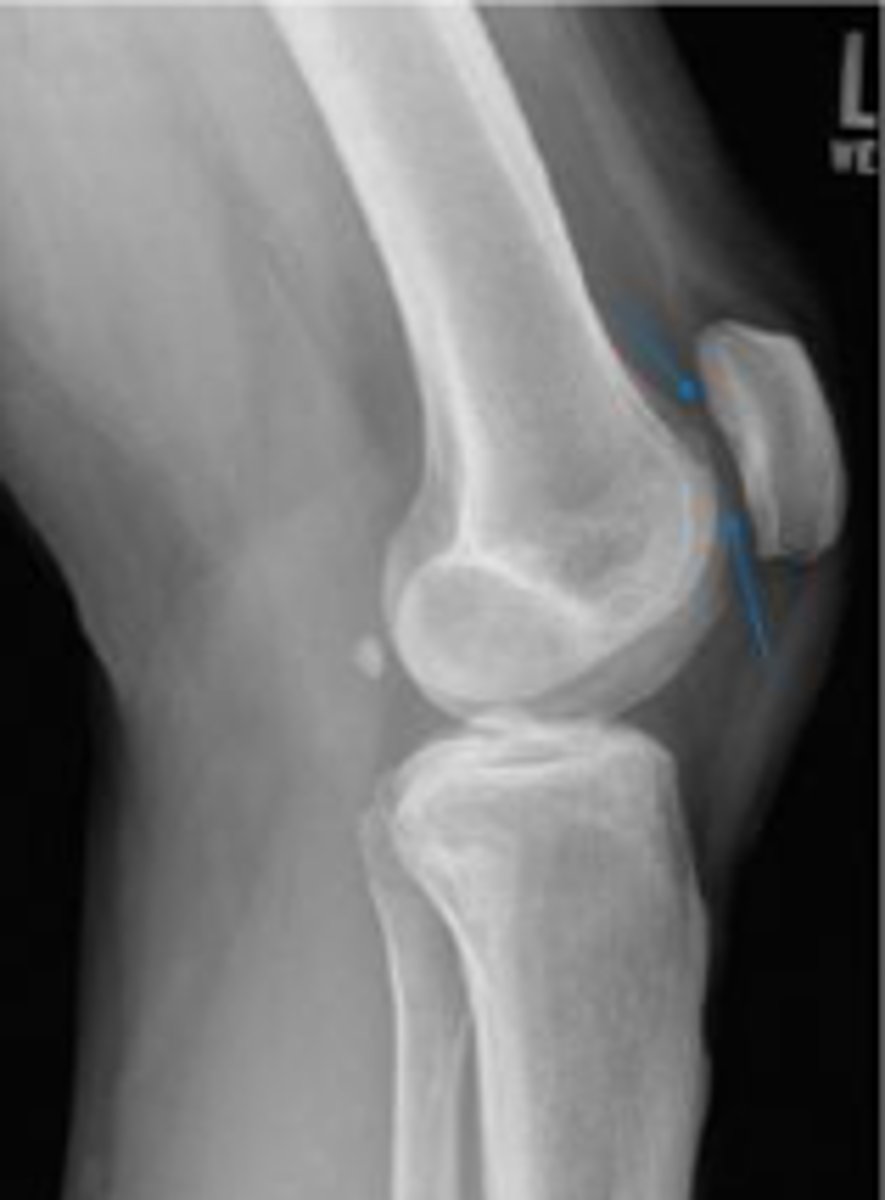

Lateral collateral ligament

What inserts at the location of the blue arrows?

Lateral collateral ligament avulsion fracture of

the right knee

What is the most significant radiographic finding?